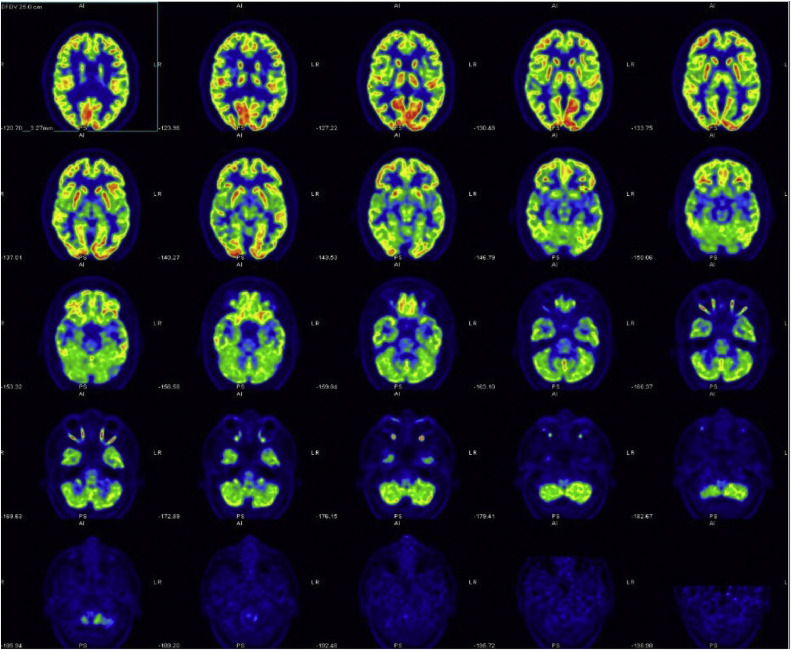

Nystagmus has various clinical manifestations, including downbeat, upbeat, and torsional types, each associated with distinct neurologic features. Current rehabilitative interventions focusing on fixation training and optical correction often fail to achieve complete resolution. When nystagmus coexists with fragile X-associated tremor/ataxia syndrome (FXTAS), functional impairments worsen, particularly affecting balance. Recognizing these limitations, the authors propose an innovative approach using audiovisual stimulation to complement visual pursuit training and optical compensation, potentially improving rehabilitation outcomes. This study describes the case of a 60-year-old woman with worsening nystagmus and cerebellar ataxia suggestive of FXTAS who underwent a customized rehabilitation program. The program included 30 sessions involving audiovisual training and physical exercises. Visual performance assessments were conducted using AV-Desk and Nidek MP-1 microperimeters, with functional assessments including the Barthel Modified Index, 10-meter walking test, timed Up and Go, and Berg Balance Scale. After treatment, visual performance improved with reduced response times and higher success rates, especially without drugs. Fixation stability improved consistently using the bivariate contour ellipse area method. Functional assessments showed enhanced mobility and balance, with benefits sustained at the 6-month follow-up. The combined approach of audiovisual training, proprioceptive training, and targeted muscle strengthening has proven effective. Notable improvements in overall physical performance, especially in balance and gait, and a reduction in nystagmus severity were observed. Integrating audiovisual stimulation into rehabilitation protocols shows promising results in managing nystagmus and ataxia, significantly enhancing patients' quality of life. Further studies are needed to validate these findings and expand upon this approach.